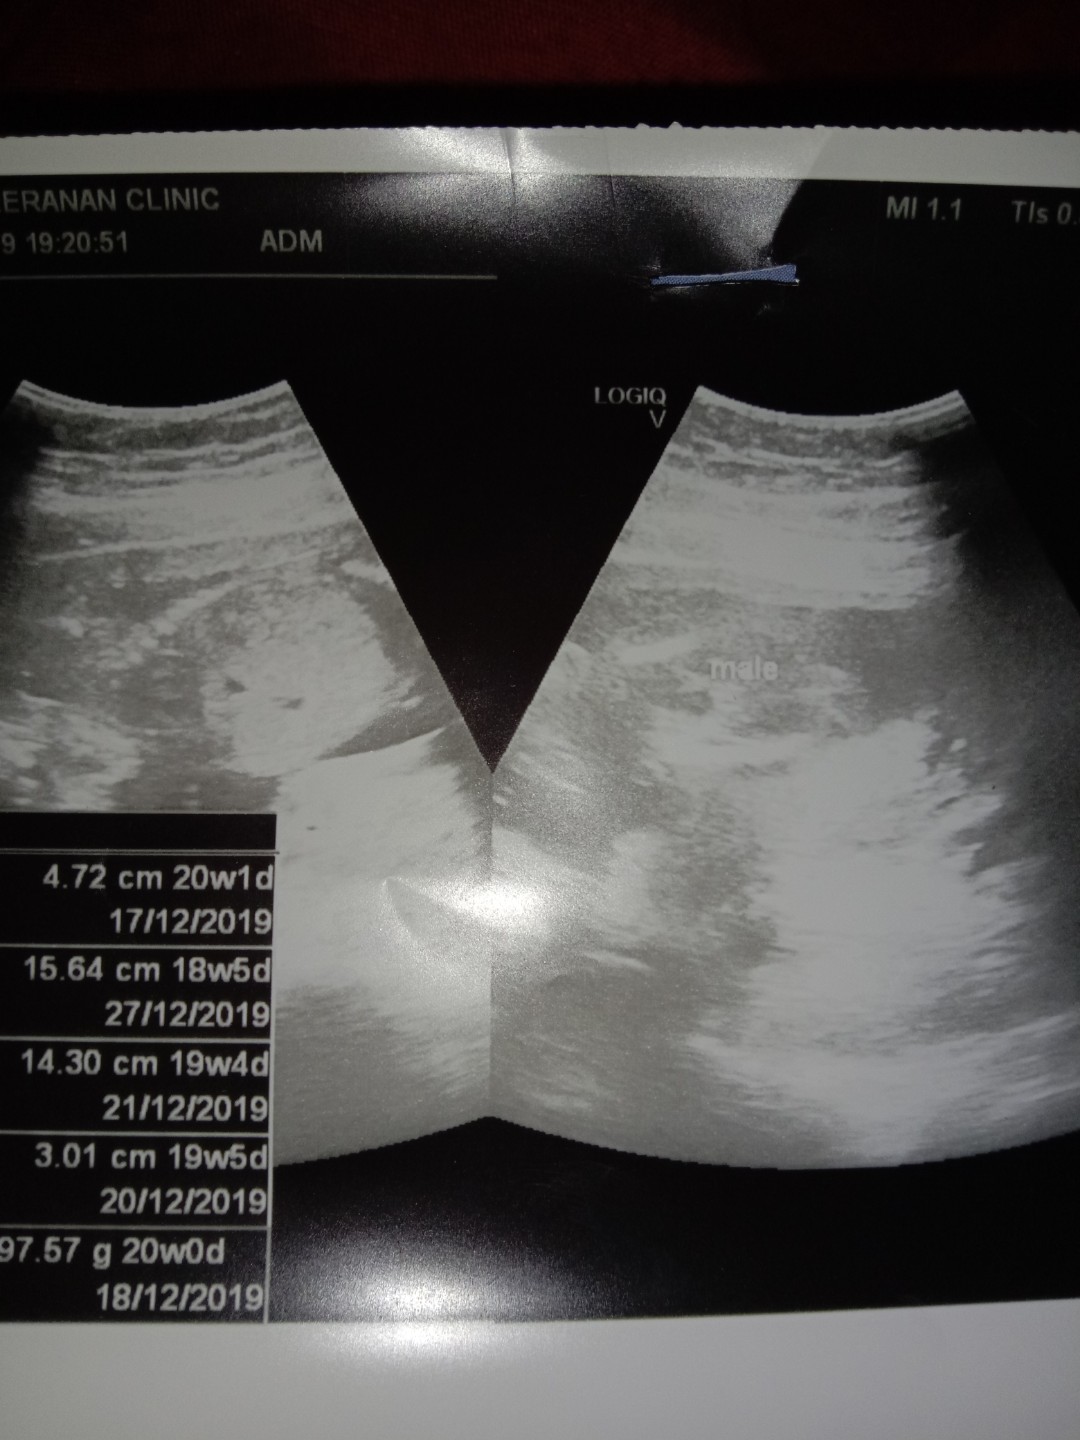

20 ธันวาคม ค่ะ ผู้ชาย